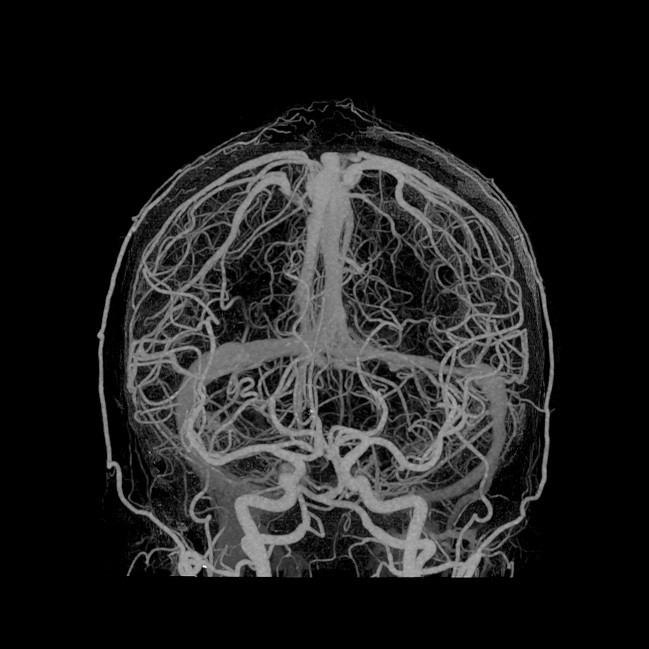

Dank künstlicher Intelligenz und neuer 3D-Rendering-Technik ist ein fotorealistischer Blick auf die Anatomie möglich.

Global Illumination von Canon Medical ist eine neue innovative 3D-Rendering-Technik, die einen präzisen und fotorealistischen Blick auf die Anatomie ermöglicht. Mittels dieses hochqualitativen alternativen Blickeindruckes wird die Diskussion unter Ärzten, mit Patienten und weiteren Gesprächspartnern (z. B. der Gerichtsmedizin) einfacher und effizienter, da die Befunde plastischer erscheinen und leichter verständlich sind. Die einfach zu bedienende Software erzeugt fotorealistische Bilder und Videos, sie wurde kürzlich erstmals der Weltöffentlichkeit im Detail vorgestellt und ist für die Vitrea-Software von Canon Medical erhältlich.

Das ultrahochauflösende Scannen in Verbindung mit der Deep-Learning-Rekonstruktion wird die Bedeutung der CT in der Diagnostik bei einer Vielzahl von Fragestellungen weiter ausbauen. Klinische Anwendungen wie Darstellungen von z. B. Lunge, Gefäßsystem, Stentstruktur oder auch die Darstellung kleiner Tumoren und Veränderungen können allesamt von der neuen Qualität profitieren.

Die integrierte, effiziente und benutzerfreundliche AiCE Deep-Learning-Rekonstruktion sorgt dafür, dass die Welt der ultrahochauflösenden Computertomographie von den Fähigkeiten des Deep-Learning besonders profitiert. Neue Rendering-Tools für die Visualisierung erleichtern den Umgang mit der Vielzahl radiologischer Daten wie die Kommunikation mit allen Beteiligten. Die Kombination des Aquilion Precision und der AiCE DLR bietet signifikante Fortschritte bei der Diagnostik, den klinischen Anwendungen, wie auch der Radionomics und definiert die Zukunft der Computertomographie.